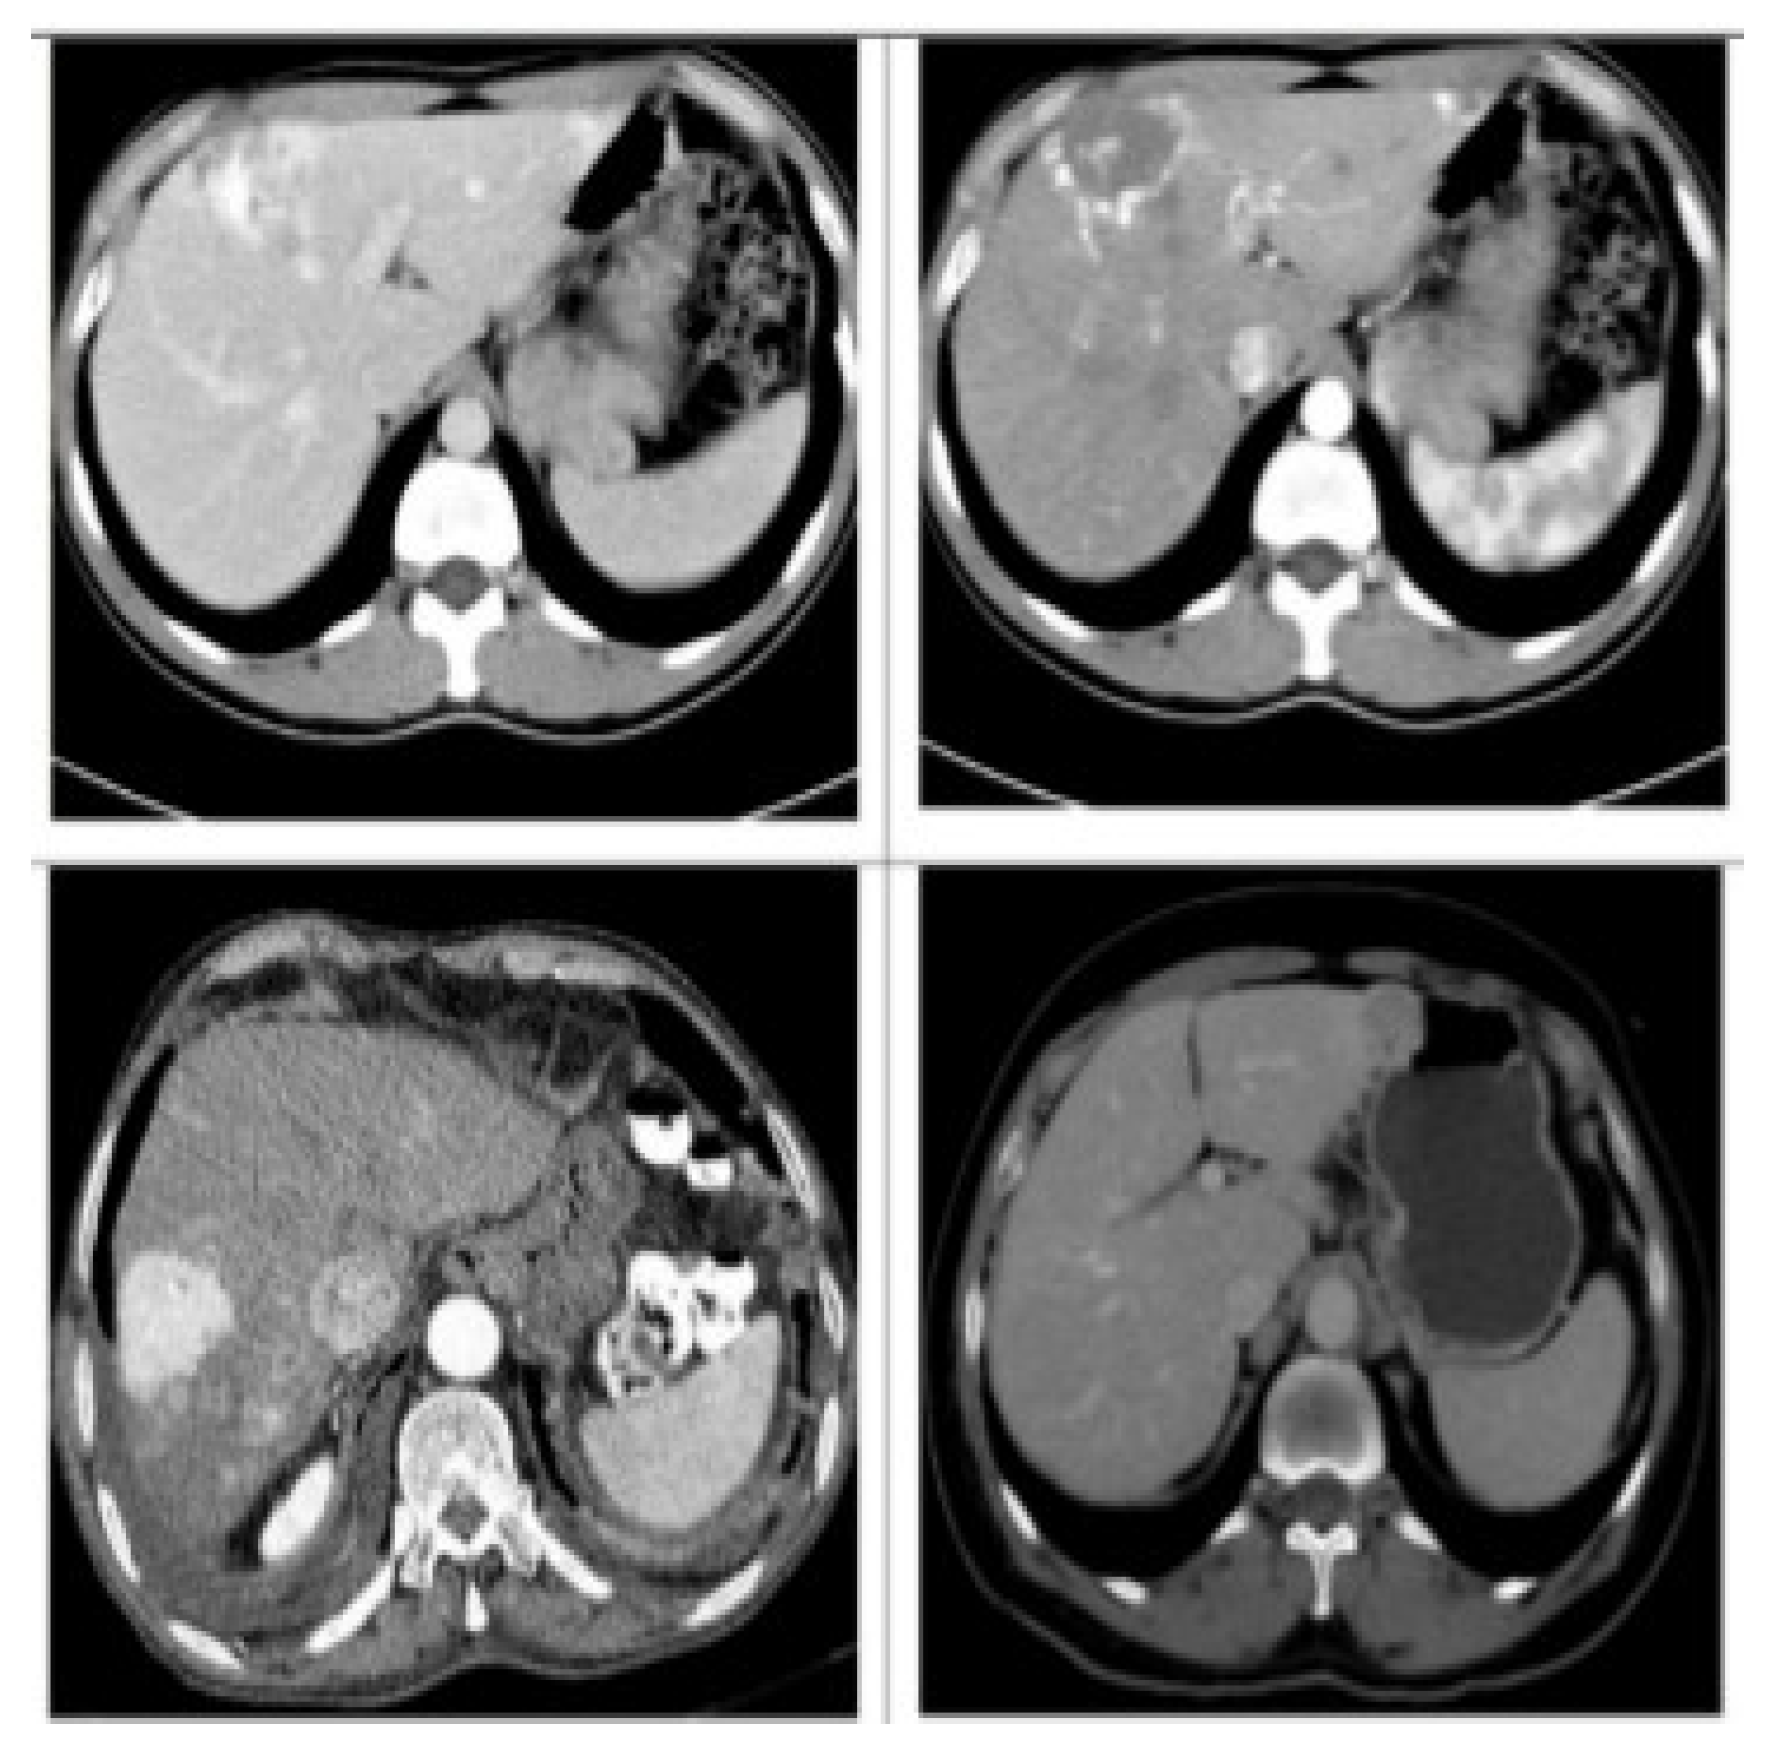

In this paper, the CT image dataset of liver lesions that were used in the study was collected from Jiangbin Hospital, an affiliated hospital of Jiangsu University (from 2015 to 2018), by searching for the medical records with hepatocellular carcinoma, metastases, hemangiomas, and healthy tissues. This work included data from 120 different patients, 30 patients with one or multiple HCC, 26 patients with one or multiple Hema, 23 patients with one or multiple Meta and 41 Heal. The dataset contains a total of 4142 images, including 1040 images of HCC, 1036 images of Hema, 1032 images of Meta, and 1034 images of Heal. From each class, 250 images were randomly selected for testing dataset, and the rest images were considered as the training dataset. Figure 5 shows the CT image samples of each lesion. An expert radiologist was in charge of marking the margins and to determine the corresponding diagnosis which was established by biopsy. Figure 6 illustrates a set of data samples from the different types. Liver lesions are different in size, shape and contrast. We preprocessed the raw in Digital Imaging and Communications in Medicine (DICOM) CT images 512 × 512-pixel metrics with a slice collimation of 5–7 mm, and 0.57–0.89 as an in-plane resolution range of slice. We have truncated the CT scan Hounsfield units (HU) values, and we normalized all slice intensities into the range [0, 1] with min–max normalization.

Figure 5.

Computed tomography (CT) images of liver lesions.